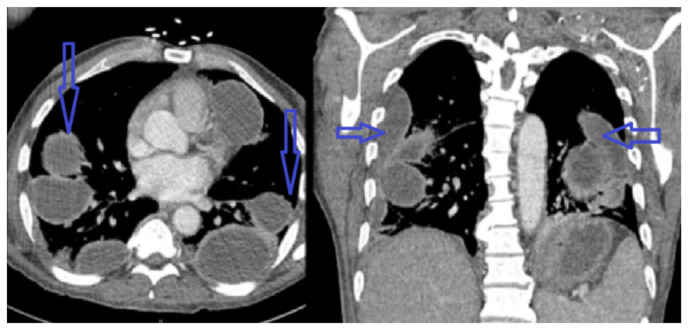

Streptococcus pyogenes is a rare cause of empyema, especially in immunocompetent individuals. The organism expresses various virulence factors leading to rapid progression of the disease. We report a case of rapidly progressing bilateral loculated empyema caused by streptococcus pyogenes in an immunocompetent host without additional risk factors.